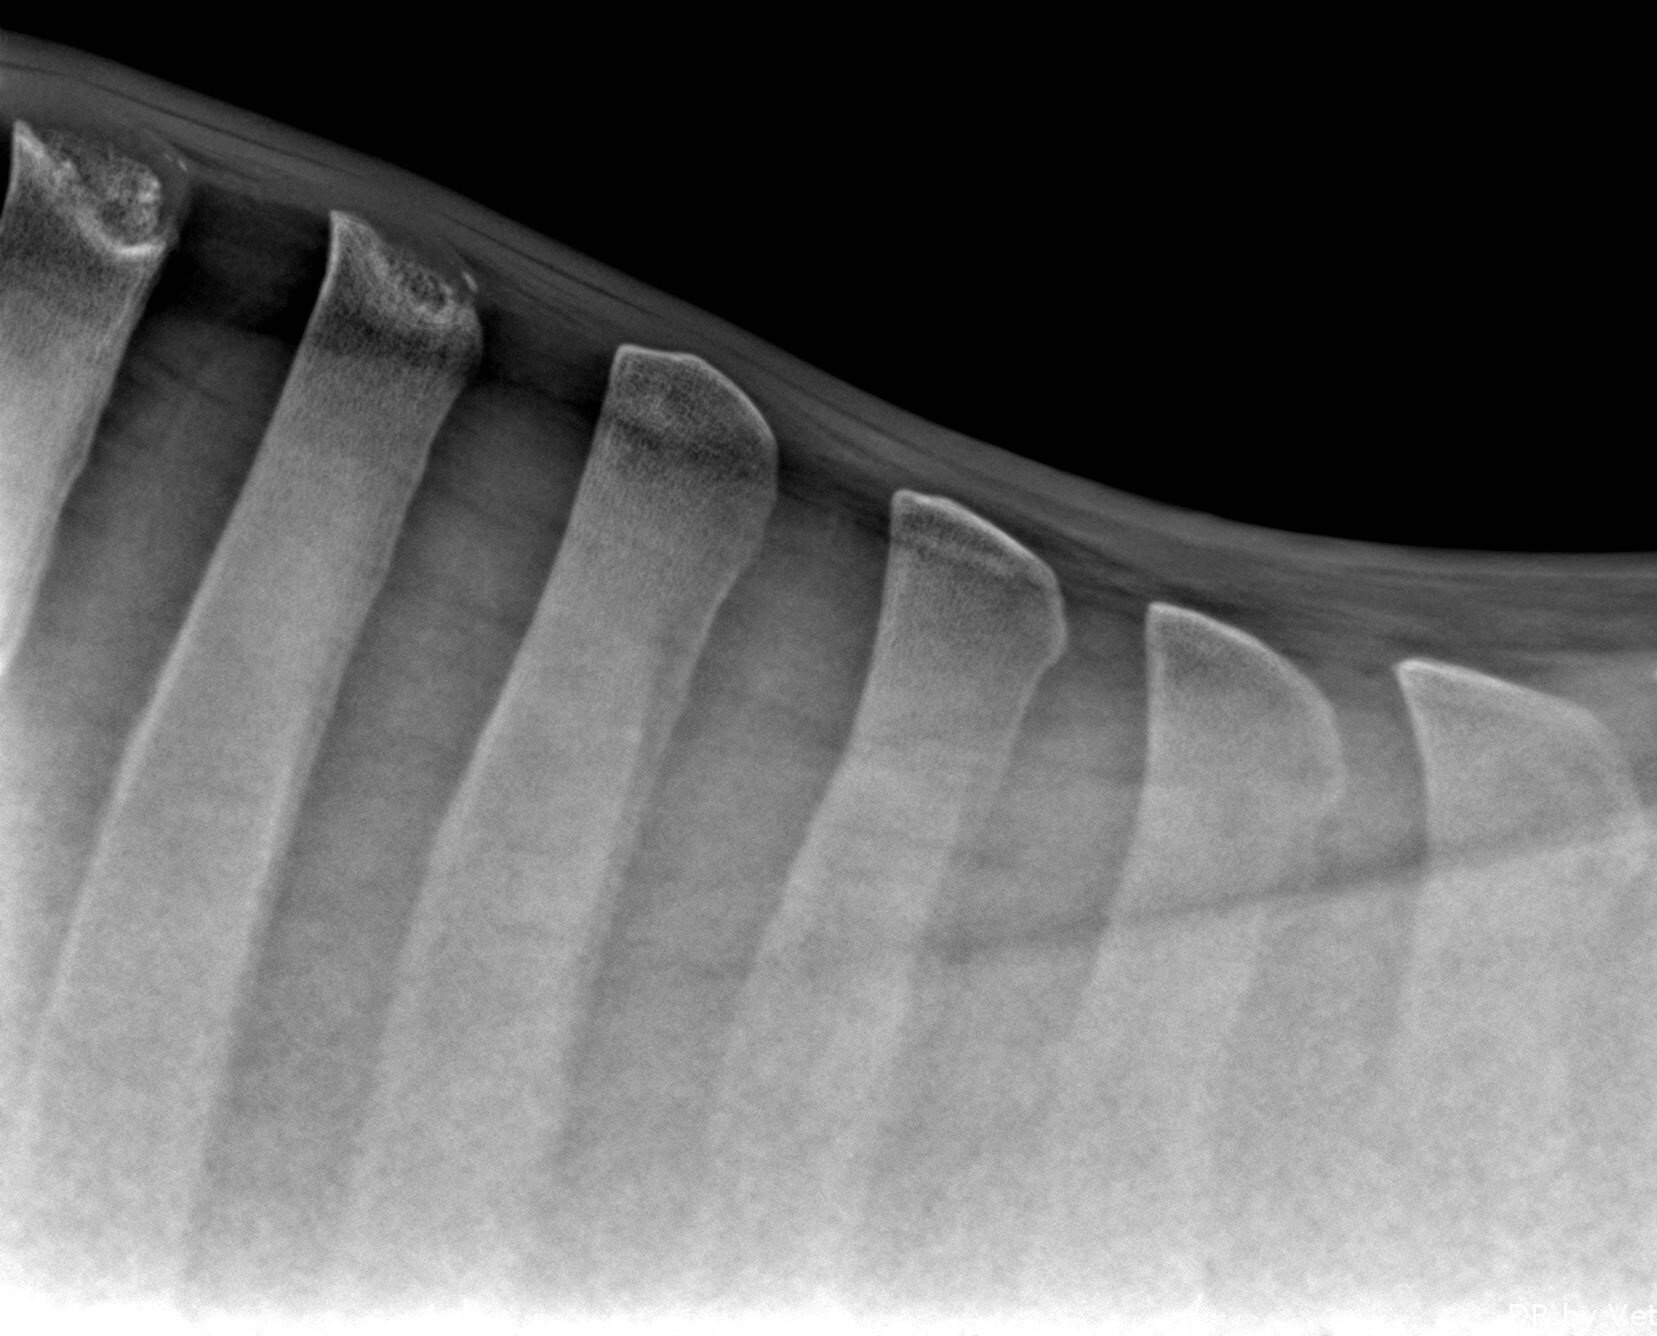

2) An orthopedic examination: inspection, palpation, movement analysis and bending tests.

This standard examination can be further supplemented by a radiological examination.

If it is desired/recommended to do further examinations afterwards, such as ultrasound, endoscopy,... this is possible.

A movement analysis is the next step in the orthopedic research. The horse is examined on the lunge on a hard and a soft surface with additional bending tests. If necessary, this examination is supplemented by a ridden examination

Once the pain site is localized, medical imaging is applied to arrive at a correct diagnosis and thus to initiate appropriate treatment.